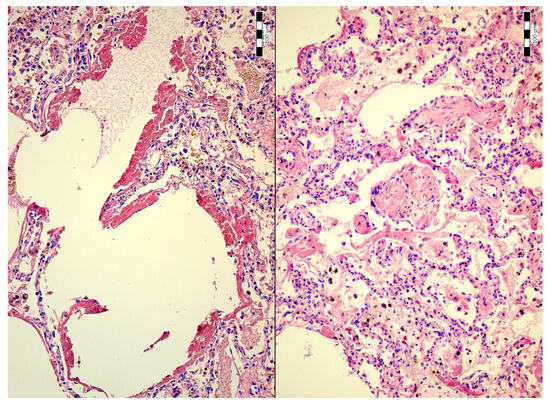

Alveolar Bile and Light Chain Immunoglobulin Depositions as an Unusual Complication of Transjugular Liver Biopsy Resulting in Bilhemia in a Patient with Multiple Myeloma

2. Case Description